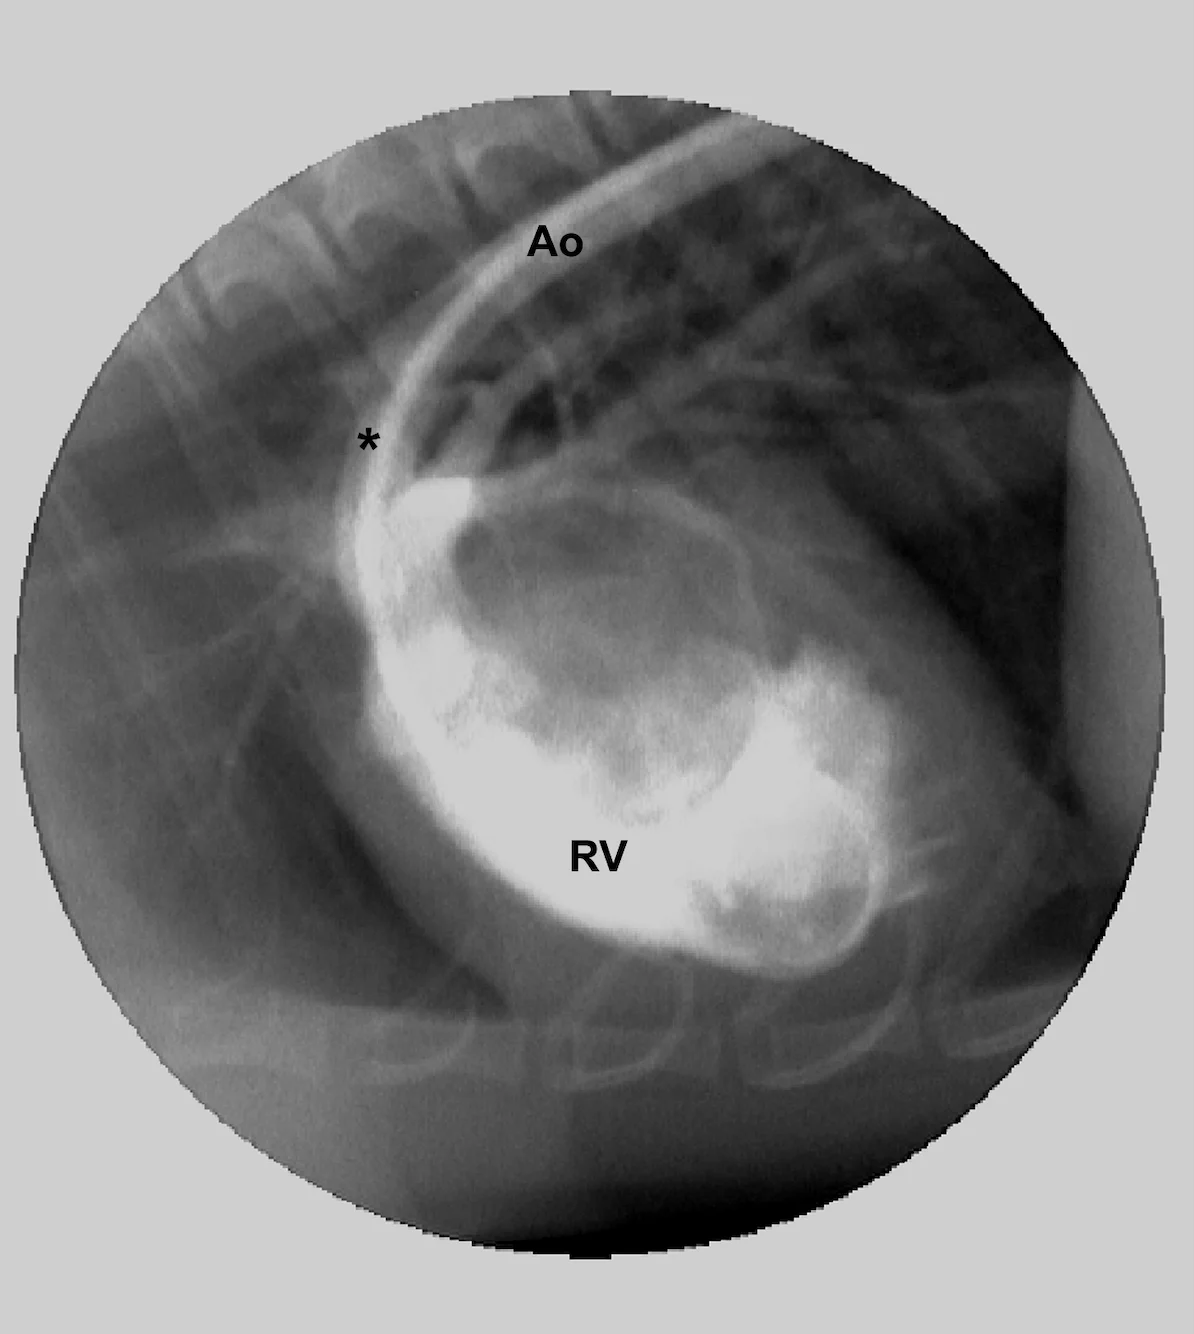

Finally, with reverse patent ductus arteriosus, only the caudal mucous membranes will be cyanotic because the brachycephalic trunk and left subclavian, which supply blood to the head and thoracic limbs, arise proximal to the site of right-sided blood entry (Figure C). This right ventricular angiogram demonstrates blood flow from the right ventricle (RV) crossing the patent ductus arteriosus (*) and into the distal aorta (Ao) in a dog with reverse patent ductus arteriosus. Note that the venous blood from the right ventricle enters the descending thoracic aorta after the origins of the brachycephalic trunk and left subclavian arteries.